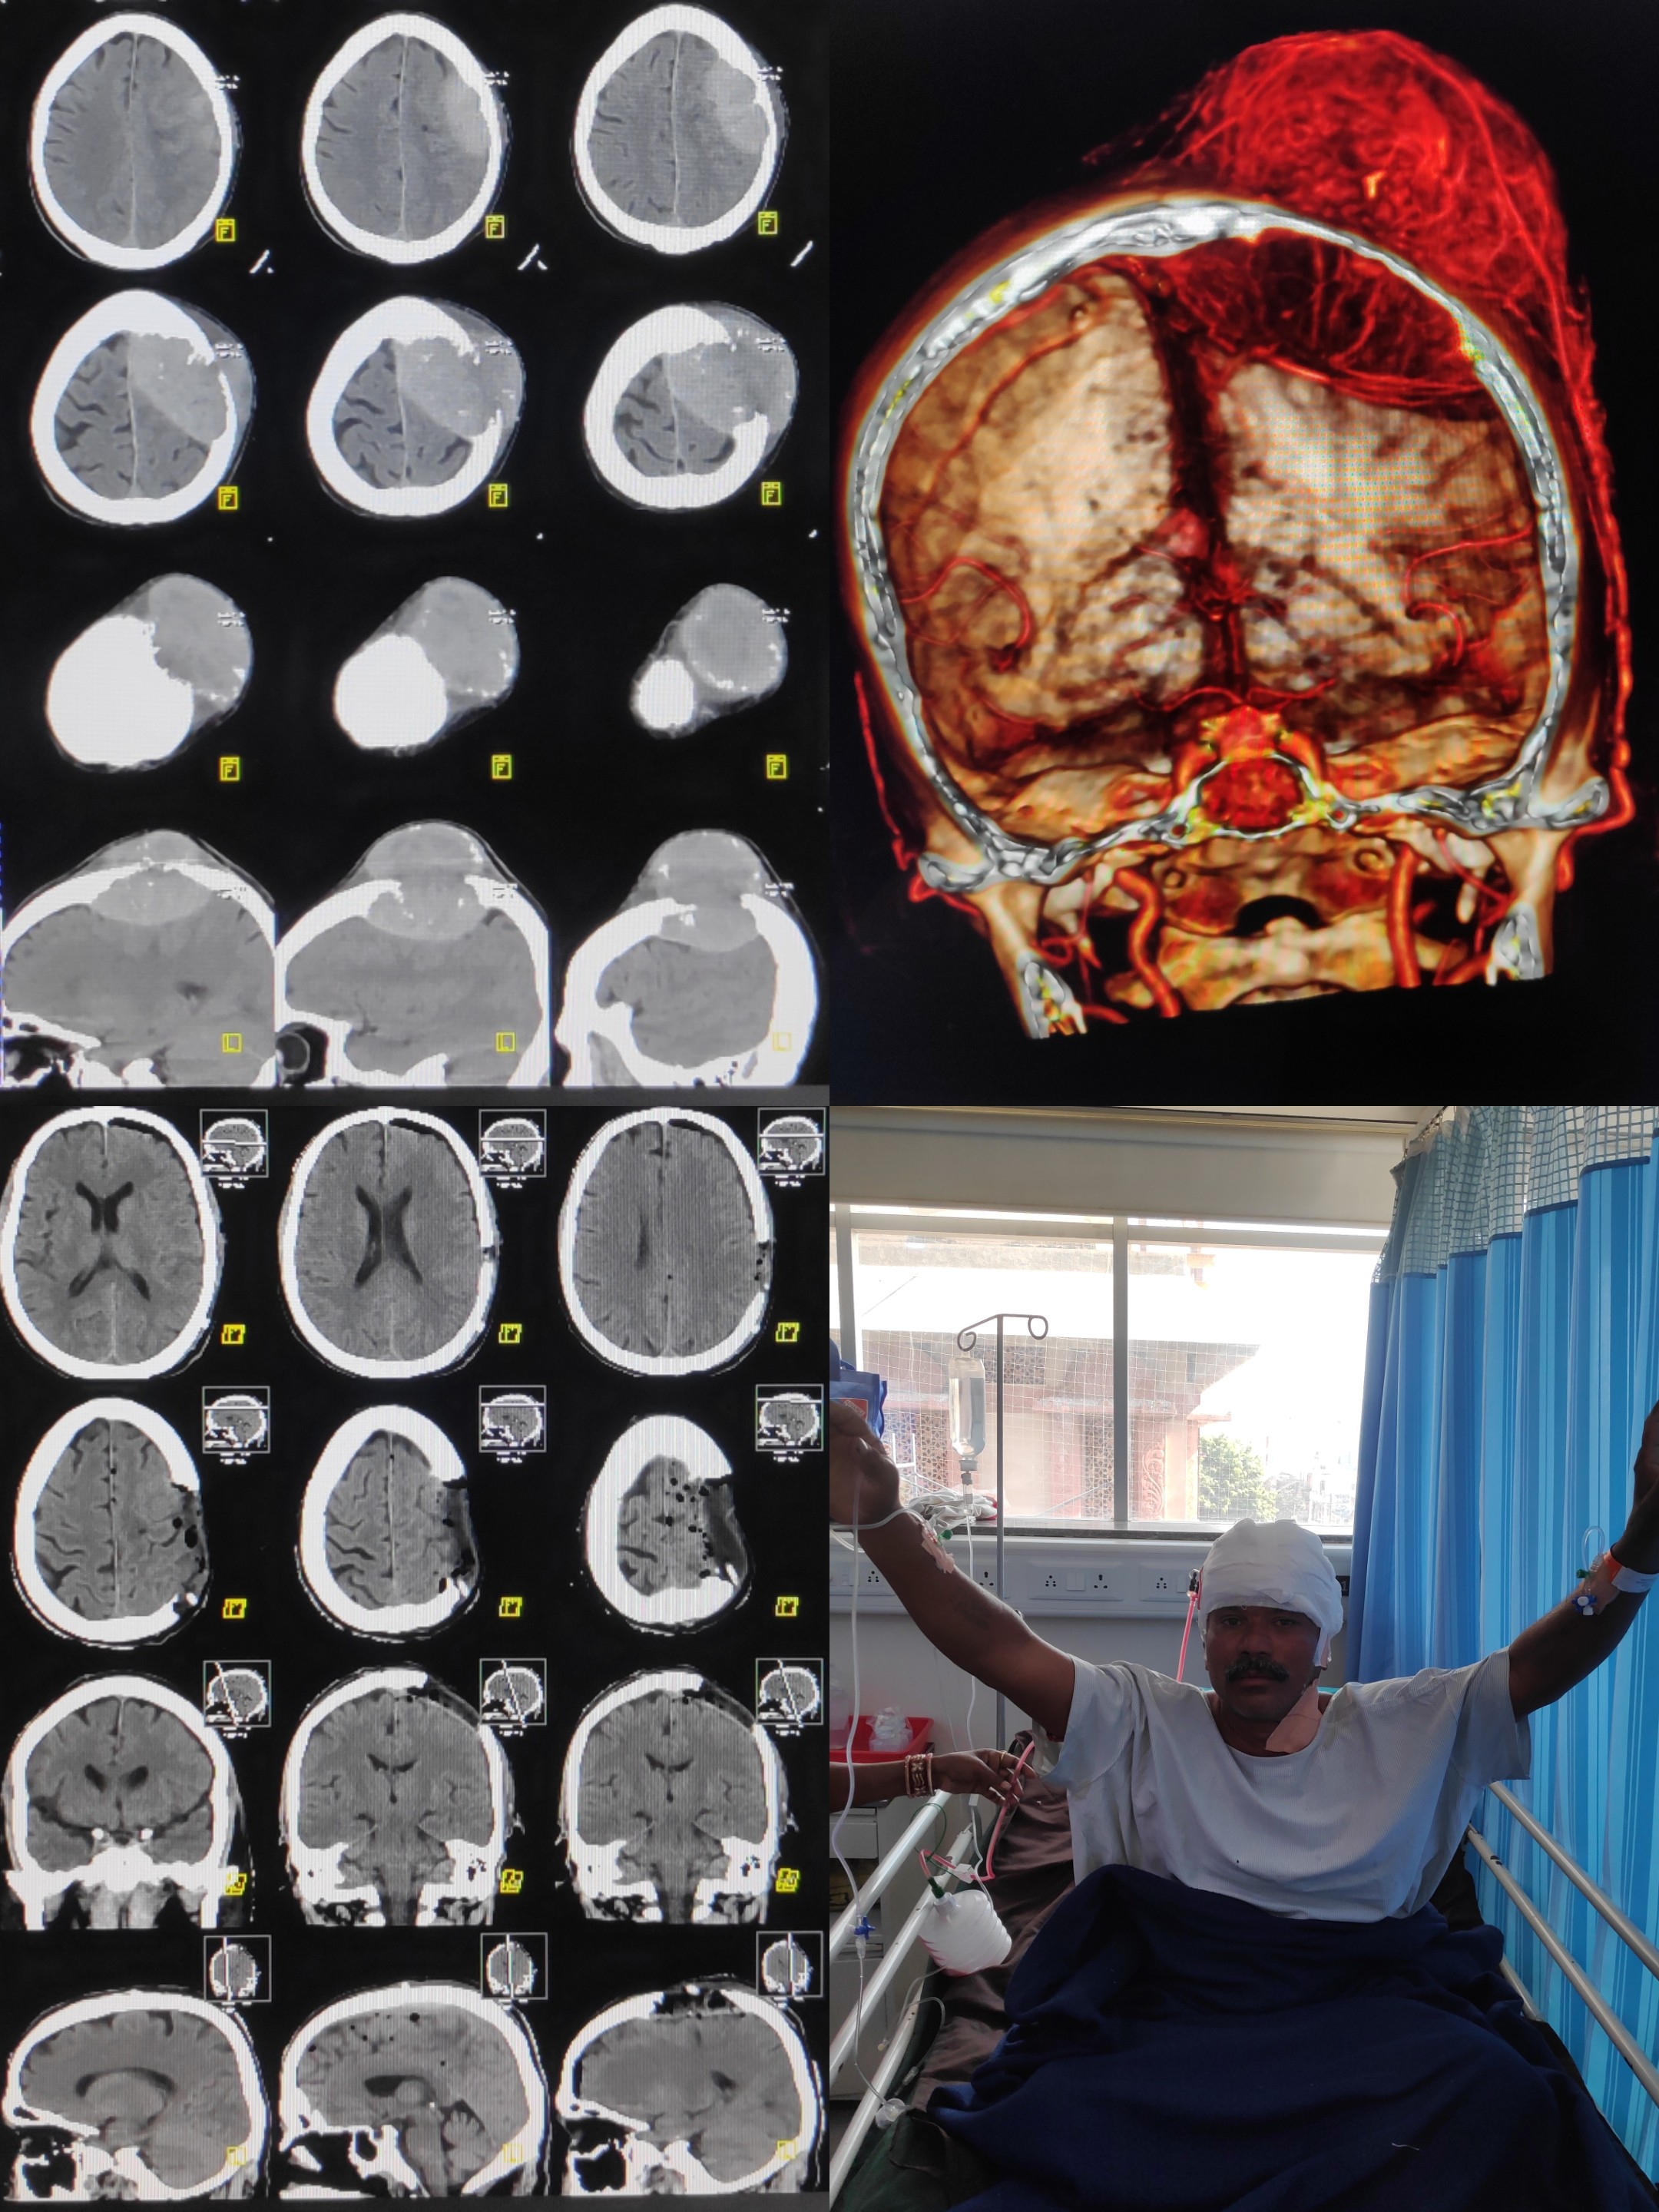

Head Injury

All kinds of trauma handling with utmost care